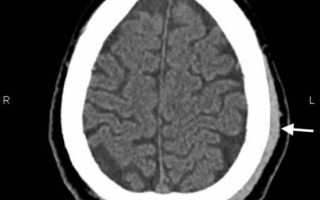

image

КТ головного мозга. Гематома периферических мягких тканей левой теменной области